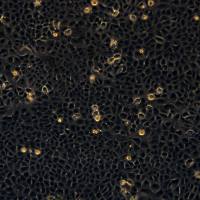

细胞图片

GES-1(人胃上皮细胞系-1)是一种经SV40病毒大T抗原永生化的人正常胃黏膜上皮细胞系。该细胞源自正常人的胃黏膜组织,其核心价值在于它保留了正常胃上皮细胞的许多形态和功能特性,例如具有典型的上皮细胞贴壁生长方式、表达角蛋白,并具备一定的分泌功能。